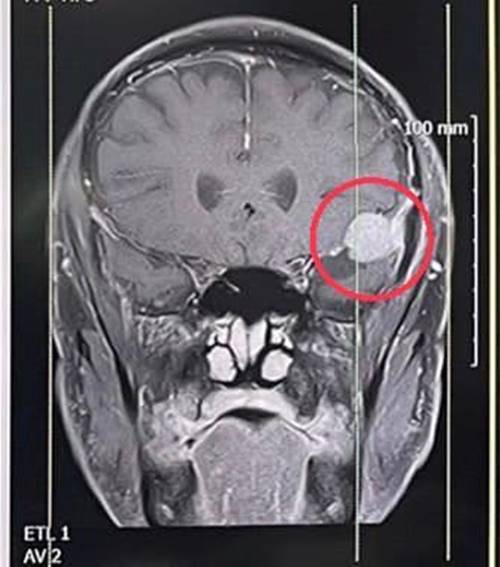

เบื้องต้น แพทย์ส่งไปตรวจแผนกหู คอ จมูก ตั้งข้อสงสัยอาจมีความผิดปกติทางสมอง จึงส่งตรวจคลื่นแม่เหล็กไฟฟ้าสมอง พบเนื้องอกในสมอง 2 เซนติเมตร จึงตัดสินใจผ่าตัด งานนี้ค่อนข้างยาก ต้องใช้ทักษะและประสบการณ์อย่างสูง เพราะนอกจากต้องแก้อาการปวดหัวให้หายเป็นปกติแล้ว ต้องไม่มีอาการแทรกซ้อนอื่น ๆ ตามมา ยิ่งก้อนเนื้อมีขนาดใหญ่ ยิ่งมีผลกระทบต่อร่างกายเท่านั้น